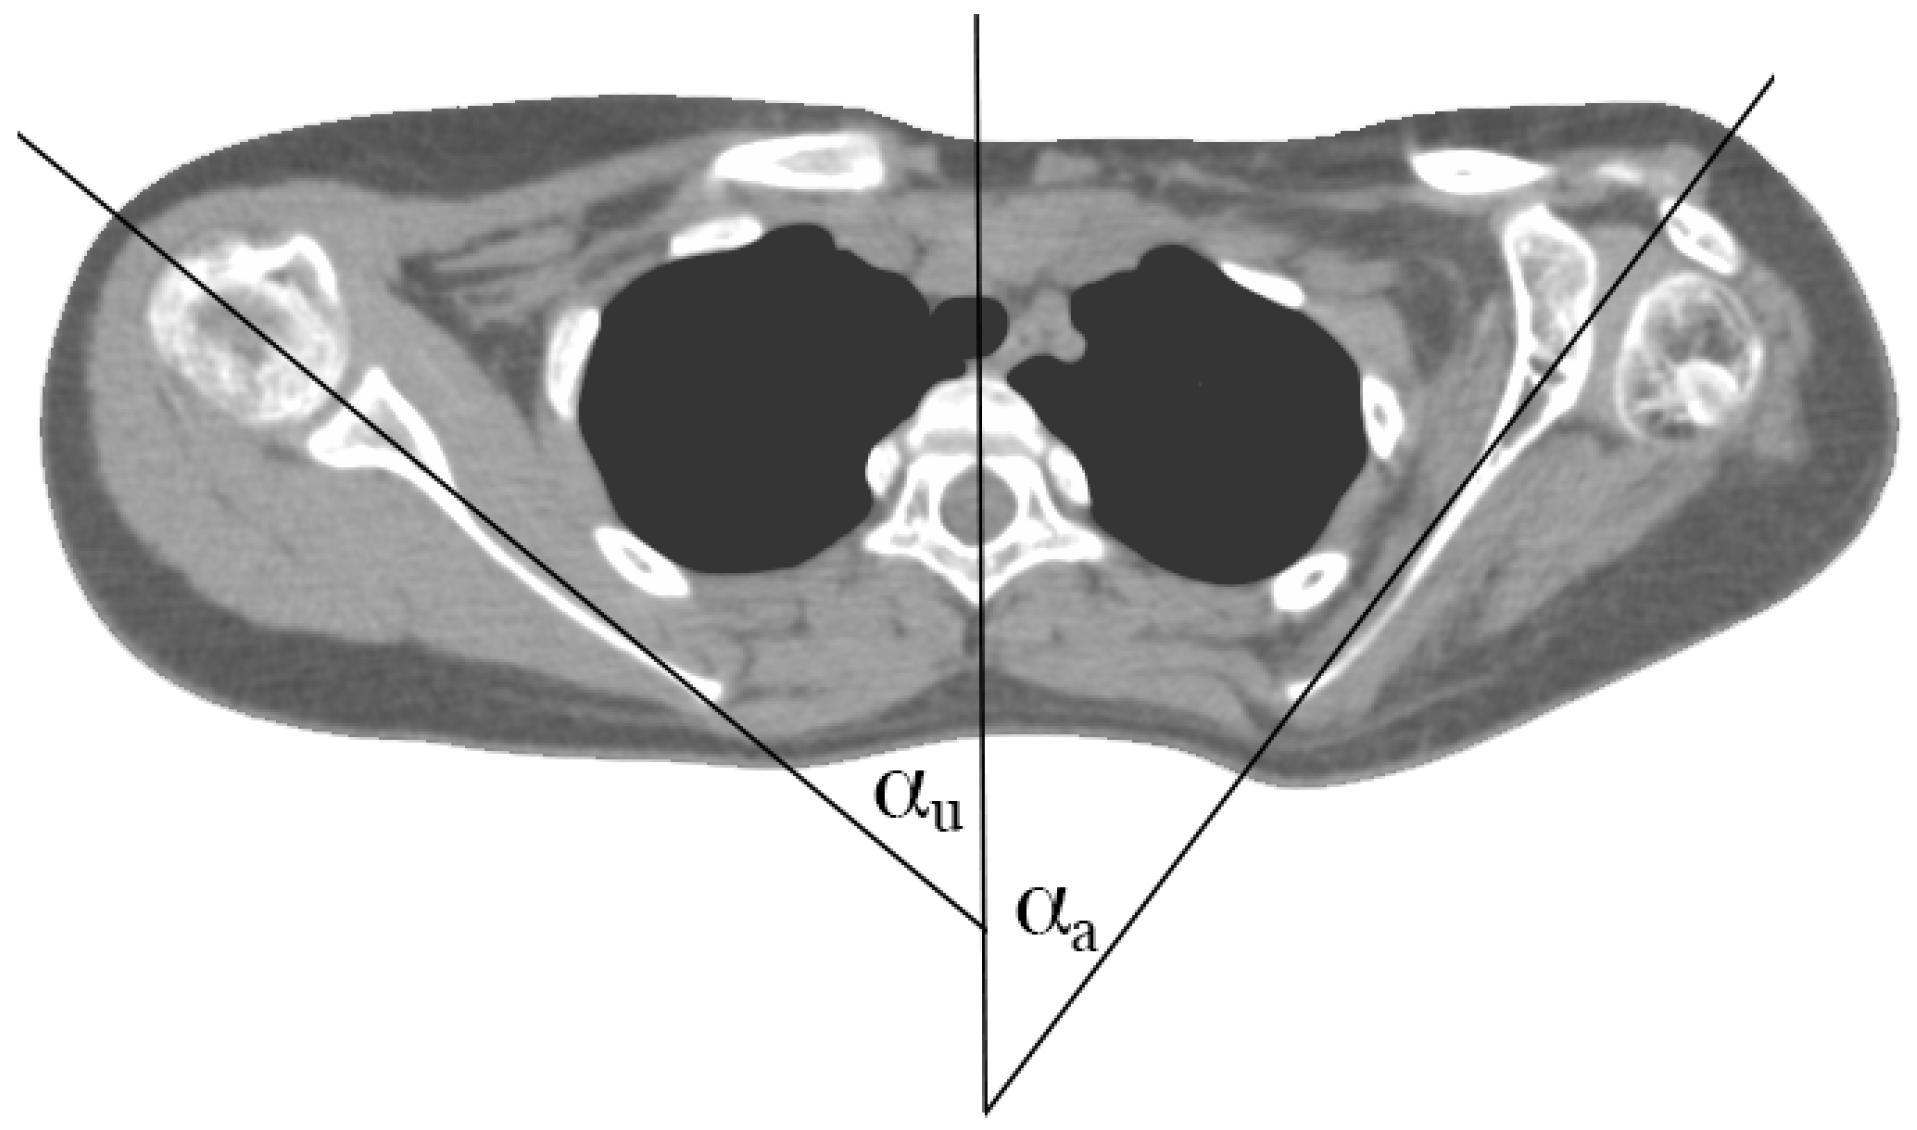

2. Materials and Methods